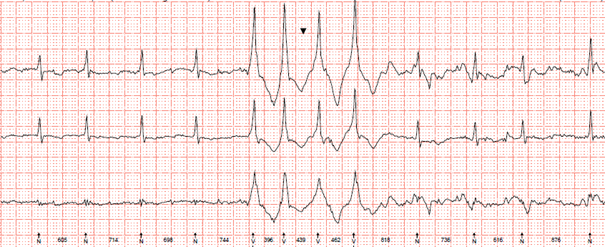

Im LZ-EKG (Bild 2) fanden sich kurze ventrikuläre Salven.

Langzeit-EKG

Bild 2: LZ-EKG